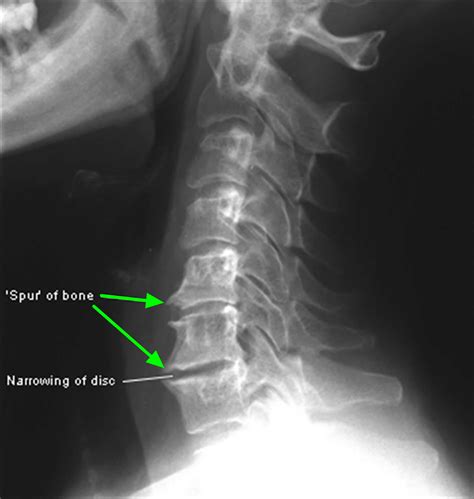

• X-Rays: X-rays can reveal the presence of bone spurs and provide information about their size and location.

Bone Spurs in the Spine

Spinal bone spurs, often associated with spinal stenosis or degenerative disc disease, can cause pain, numbness, and weakness in the back, neck, arms, or legs. Treatment options include medications, physical therapy, and in severe cases, surgery to remove the spurs and decompress the spinal cord or nerves.